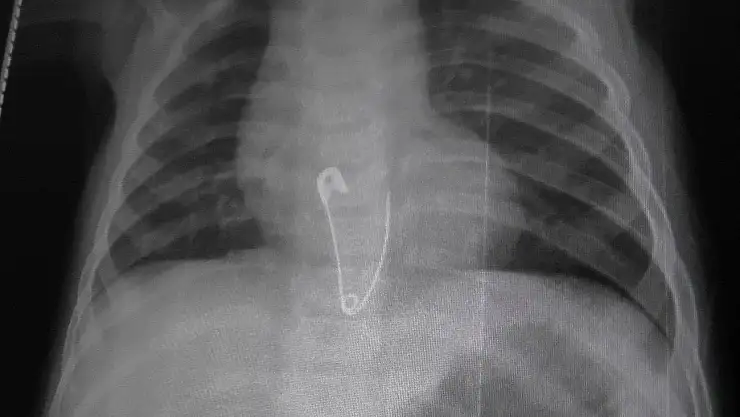

Edinilen bilgiye göre, 8 aylık olan T.N.Y. evde sehpa üzerinde bulunan çengelli iğneleri alarak oynamaya başladı. Bir süre sonra ailesi tarafından fark edilen bebeğin oynağı iğnelerin eksik olduğu anlaşıldı. Yapılan aramada eksik olan çengelli iğneyi bulamayan aile, çengelli iğneyi bebeklerinin yutmuş olabileceğini düşünerek Kulu Devlet Hastanesi’ne başvurdu. Çekilen röntgende çengelli iğnenin bebeğin yemek borusunda olduğu belirlendi. Bunun üzerine 8 aylık bebek iğnenin çıkarılması için Ankara’ya sevk edildi.